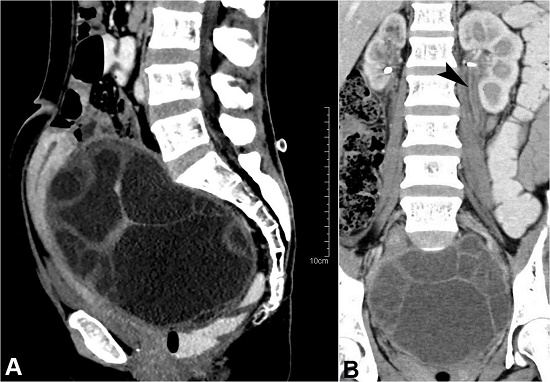

A 37-year-old nulliparous woman sought medical care complaining of progressive increment of the abdominal girth over the last year. She had significant weight loss and low-grade fever for the last month. She had no associated history of nausea, vomiting, diarrhea, anorexia, or jaundice. Her menses were irregular since then, and micturition was difficult demanding urinary catheterization. Her medical history was unremarkable. She was a daily wage laborer working on a farm with a recent history of traveling from central India. The abdominal examination revealed a palpable firm irregular mass arising from the pelvis. She was admitted with the working diagnosis of ovarian cystadenoma and ipsilateral hydroureteronephrosis. The routine blood biochemistry, urine examination, and chest X-ray were normal. The alpha-fetoprotein (AFP), carcinoembryonic antigen (CEA), cancer antigen 15-3 (CA 15-3), and cancer antigen 125 (CA 125) were normal. The contrasted-enhanced computed tomography (CECT) scan of the abdomen and pelvis revealed a large (14.8x12.6x9.5 cm) multiseptated cystic lesion in the Pouch of Douglas, consistent with the ovarian origin and ipsilateral hydroureteronephrosis (Figure 1A and 1B). Imaging findings mimicked an ovarian cyst.